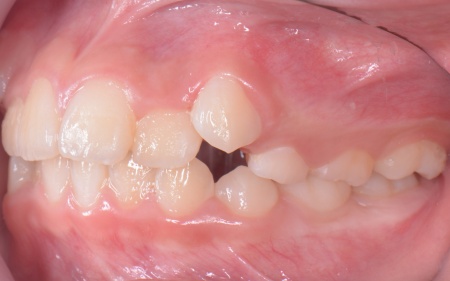

拝見したところ、上の犬歯が歯列の外側に飛び出すように生えている、いわゆる八重歯でした。

さらに、上下の歯全体がデコボコに生えている「叢生(そうせい)」と呼ばれる状態で、これは歯が正しい位置に並ぶためのスペースが不足していることが原因だと考えられます。

このまま放置して顎の成長が完了してから矯正治療を行う場合、歯を並べるスペースを確保することが難しく、永久歯を抜く処置が必要になるケースがあります。

患者様のご家族は「将来的な抜歯はできるだけ避けたいので、今のうちに治療をしたい」と希望されたため、成長期の段階で歯列を広げ、歯が並ぶスペースを確保する小児期の矯正治療「1期矯正」を提案しました。